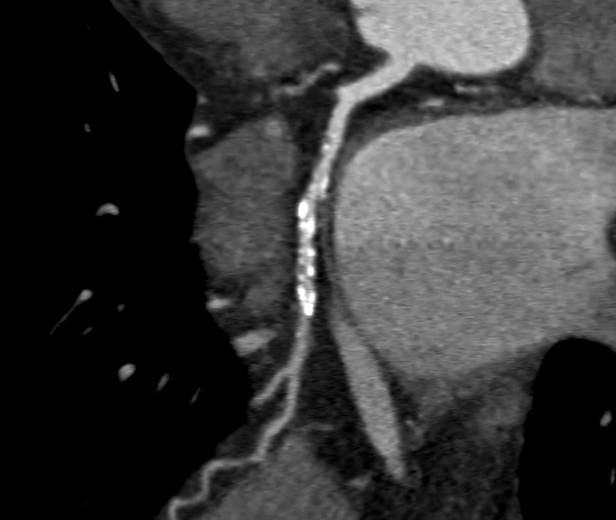

Cardiac CT

CARDIAC CT. Explained.